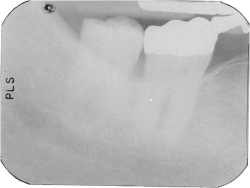

| A typical underexposed shot. These images cannot be corrected digitally. |

Exposure errors. Once again, says Williamson, don't rely on default settings. "Look at your subject! A big guy needs a longer exposure, a small 80 year old woman, much less," says Williamson. Underexposed shots can't be corrected digitally, she says. Overexposed pictures can be fixed. "But the more you fuss with an image, the worse it gets."